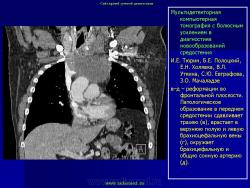

Средостение.  "Опухолевый рост".

Продолжение.